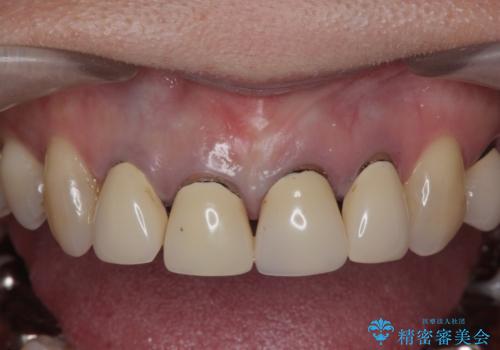

- 「黒ずみの前立つ前歯をやりかえ、きれいにしたい。」と希望され来院されました。

金属色の目立つ前装冠を除去し、発生していた小さな虫歯を丁寧に全て除去しジルコニアセラミッククラウンで審美的な前歯となるような治療を計画します。

金属を用いないジルコニアセラミッククラウンは透明感の再現性に優れ、審美性と自然な仕上がりの両立を期待することができます。